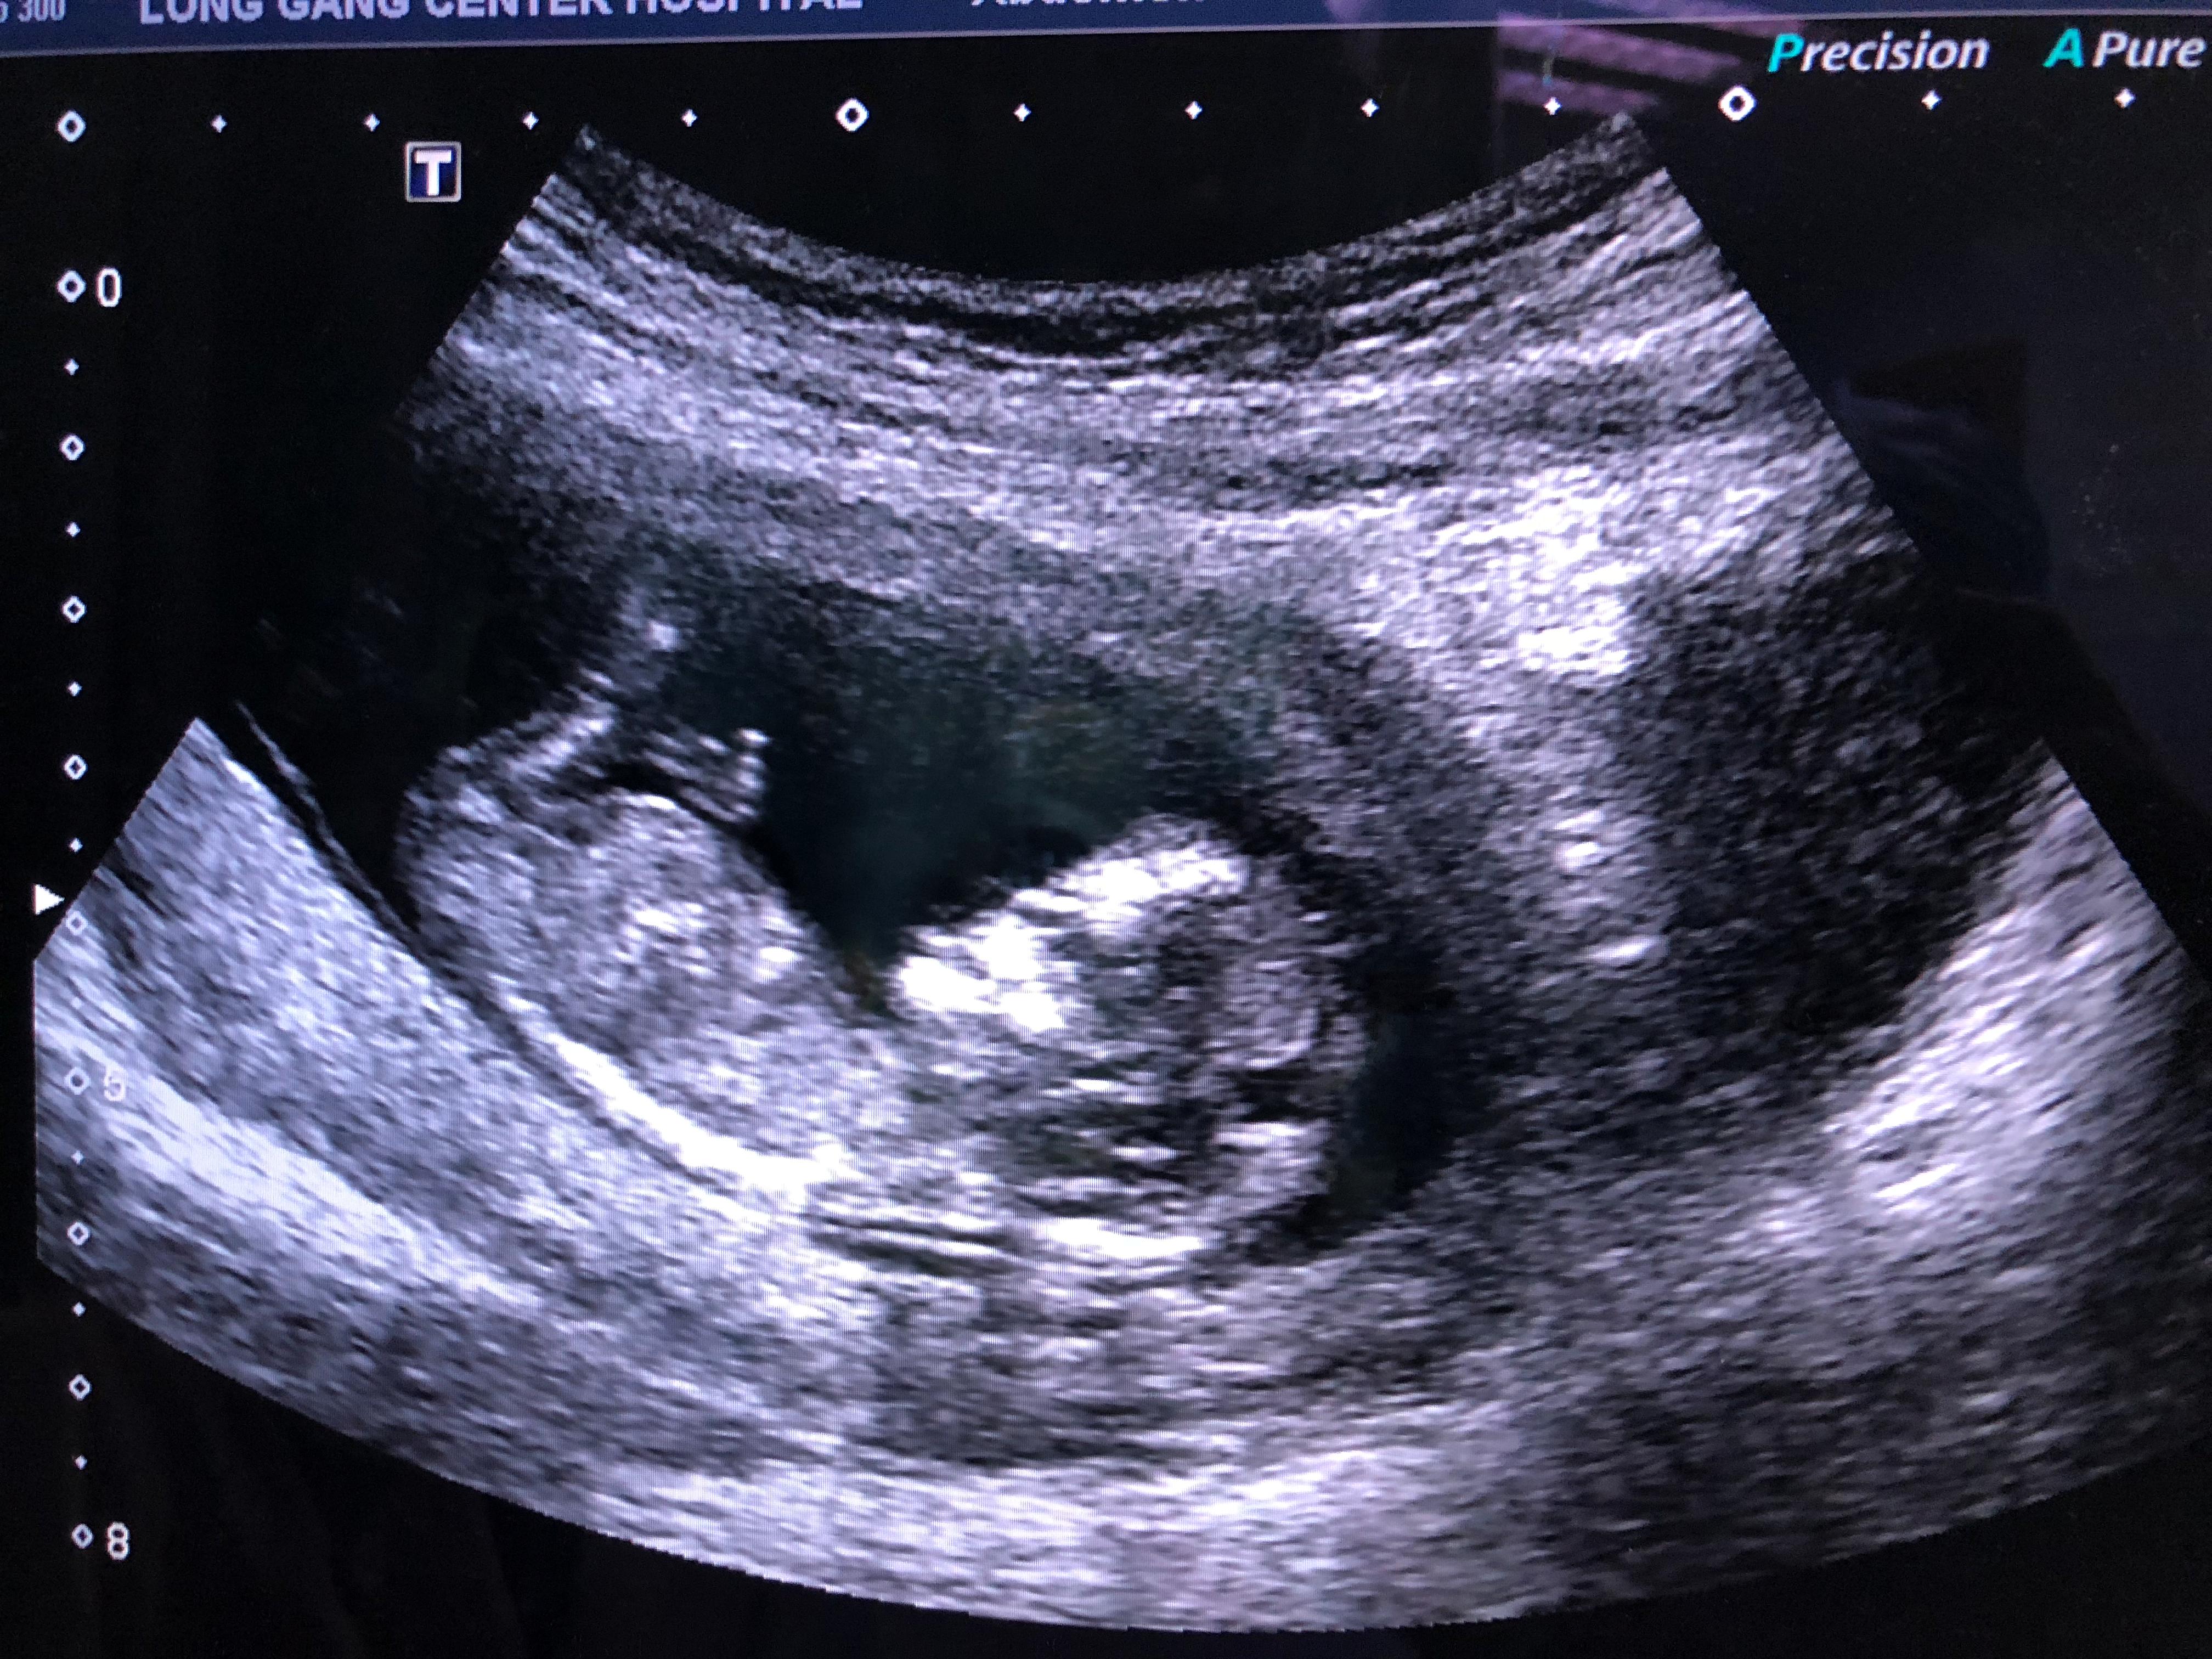

先跟大家汇报一个好消息,小小超人NT过关啦,目前15+周,先放个靓照压压场子。

小小超人,妈妈爱你哦~